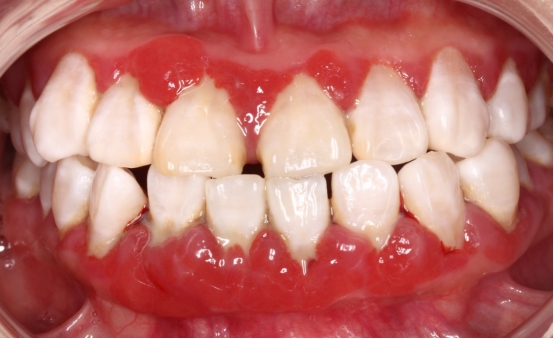

牙周炎是累及四种牙周支持组织(牙龈、牙周膜、牙槽骨和牙骨质)的慢性、炎症性、破坏性疾病。牙周最重要的支持组织就是牙槽骨,就犹如大树深深扎根在土壤中一样,我们的牙齿也牢牢的附着在牙槽骨内。当牙周炎症时,牙槽骨就会被吸收破坏,造成牙齿的“水土流失”,最终致使牙齿松动甚至脱落。

牙龈出血

刷牙出血是牙龈炎症最早且最容易发现的症状,也是牙周组织最先发出的危险警告。如果使用一些含止血成分的药用牙膏,这种牙龈炎症的“报警”就会被掩盖,导致牙周炎症继续进展,进而造成牙槽骨的炎症。

牙龈萎缩及牙齿敏感

当我们的牙槽骨萎缩时,牙龈会跟着萎缩,牙龈萎缩会导致牙根暴露,继而出现牙齿敏感。